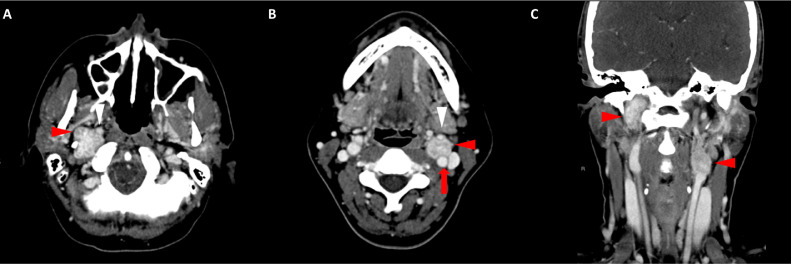

頸部增強 CT 顯示 2 個強烈強化的腫塊。 一個位于頸部右側,位于右側頸內動脈后方的頸動脈間隙中,位于莖突內側,大小為 24 × 24 × 30 mm,頸靜脈橫向移位(圖 1A)。 第二個位于左側頸動脈間隙,在分叉處正上方展開頸外動脈和頸內動脈,尺寸為 15 × 18 × 22 mm(圖 1B)。 影像學檢查結果與右側迷走神經和左側頸動脈體副神經節(jié)瘤一致,與之前的活檢結果一致。

圖1:右側迷走神經和左側頸動脈體副神經節(jié)瘤。 (A) 軸位增強 CT 顯示右側頸動脈間隙、右側頸內動脈后方(白色箭頭)和莖突內側有強烈強化的腫塊(紅色箭頭)。 (B) 軸位對比增強 CT 顯示左頸動脈間隙有強烈強化的腫塊(紅色箭頭),向后張開頸內動脈(紅色箭頭),向前張開頸外動脈(紅色箭頭)。 (C) 冠狀對比增強 CT 顯示兩個增強腫塊(紅色箭頭)。